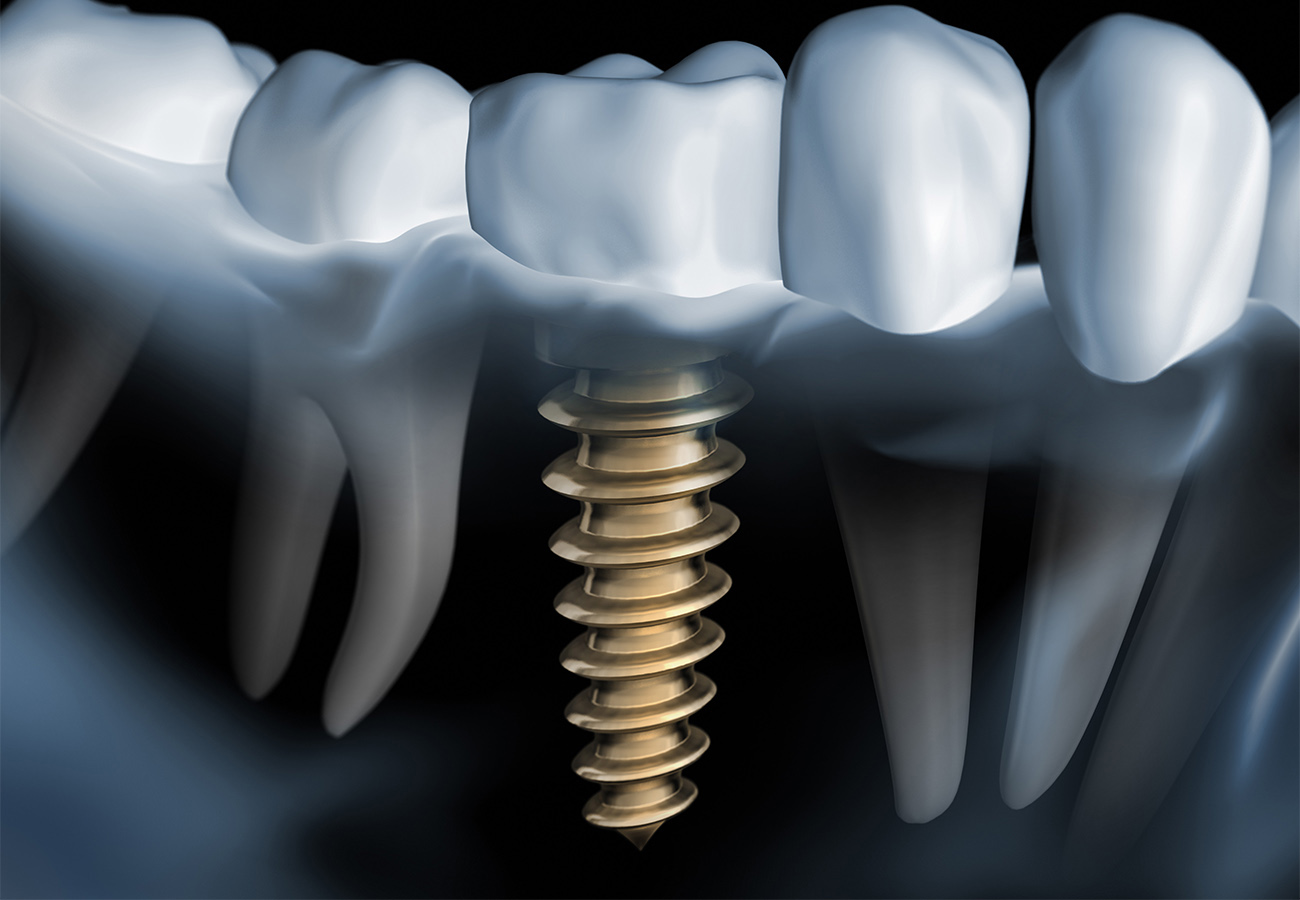

Зубы на черном фоне: Визуализация стоматологических изображений

Раздел: Необычные решения